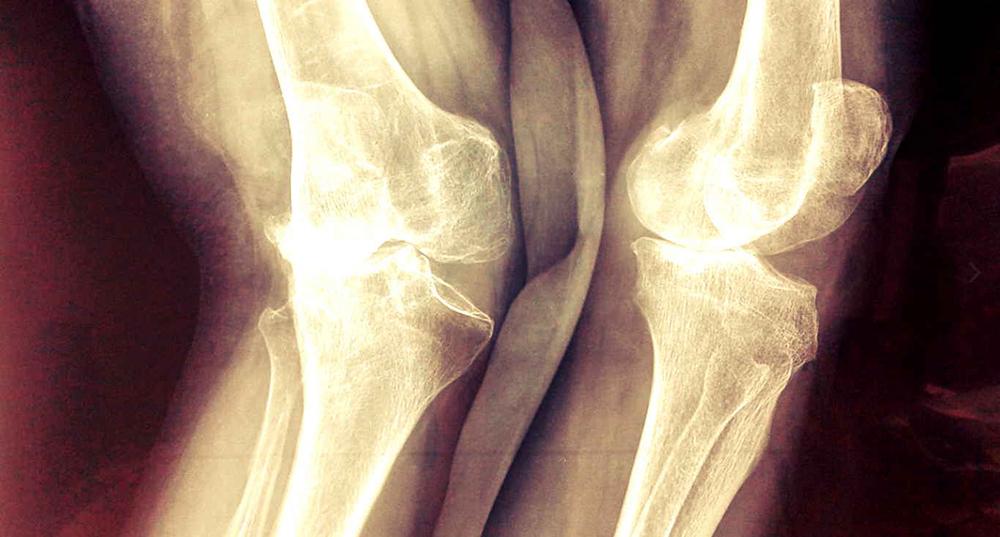

Остеоартроз — хроническое заболевание суставов, которое прогрессирует и при котором нарушается метаболизм и структура суставного хряща, что приводит к его дистрофии.

На поздних стадиях болезни разрушаются суставные поверхности, появляются остеофиты.